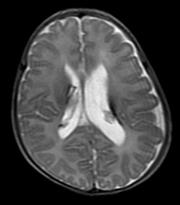

【111-1 醫學(四) 第74題】懷孕週數20週出生的早產兒,出生後2個月出現腦室擴大,其T2加重磁振造影像可見腦室壁上的低訊號病灶如圖,最可能原因為何?

詳解

破題關鍵

本題的關鍵在於「20週早產兒」、「出生後2個月腦室擴大」以及T2加重磁振造影上「腦室壁上的低訊號病灶」。這些線索強烈指向早產兒常見的腦部出血及其後遺症。